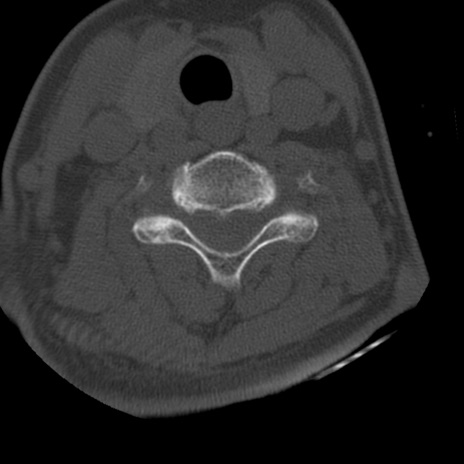

症例50 頚椎CT(横断像)

頚椎CT